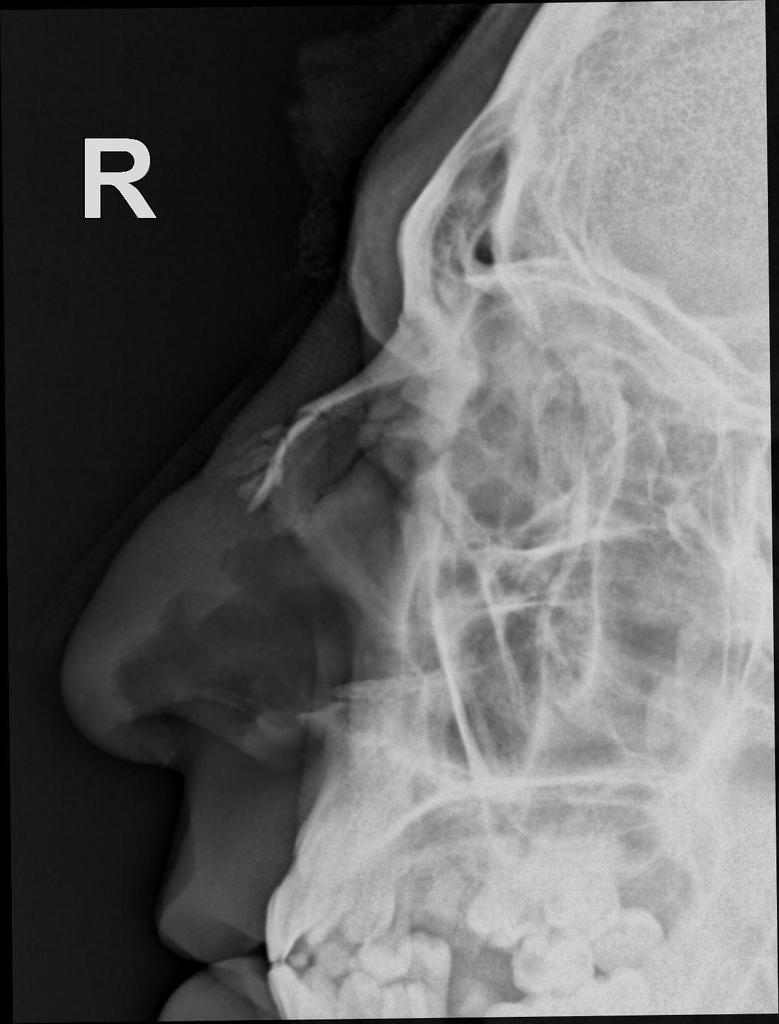

٤/ كسور الرقبه والعمود الفقري: طبيب جراحة العمود الفقري أو طبيب جراحة المخ والأعصاب هم المسؤولين عنها.